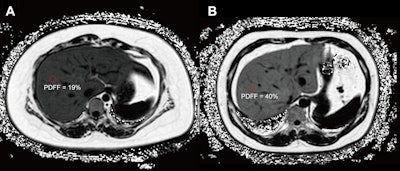

Axial proton density fat fraction (PDFF) maps show hepatic steatosis assessment in patients with dysglycemia. (A) PDFF map in a 27-year-old female patient (body mass index [BMI; calculated as weight in kilograms divided by height in meters squared] = 38.9) with a 1-year history of obesity and metabolic syndrome, and hospital-confirmed prediabetes. The image shows moderate hepatic steatosis (mean liver PDFF, 19%; circle). (B) PDFF map in a 40-year-old male patient (BMI = 33.35) with a history of obesity, metabolic syndrome, hypertension, and hospital-confirmed type II diabetes. The image shows severe hepatic steatosis (mean liver PDFF, 40%; circle).Axial proton density fat fraction (PDFF) maps show hepatic steatosis assessment in patients with dysglycemia. (A) PDFF map in a 27-year-old female patient (body mass index [BMI; calculated as weight in kilograms divided by height in meters squared] = 38.9) with a 1-year history of obesity and metabolic syndrome, and hospital-confirmed prediabetes. The image shows moderate hepatic steatosis (mean liver PDFF, 19%; circle). (B) PDFF map in a 40-year-old male patient (BMI = 33.35) with a history of obesity, metabolic syndrome, hypertension, and hospital-confirmed type II diabetes. The image shows severe hepatic steatosis (mean liver PDFF, 40%; circle). RSNAAccording to the results, the researchers found a dose-response relationship between liver PDFF and abnormal glucose metabolism. Specifically, each 1% increase in PDFF was associated with higher odds of both prediabetes and type II diabetes (odds ratio [OR], 1.04; p